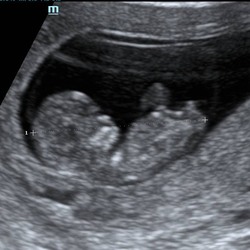

Wij zijn op kerstdag naar spoed gereden voor hetzelfde… had ook opgezocht van wanneer het voorkwam en dacht dat ik veel te vroeg was. Na urine en bloed onderzoek, hebben ze echotje gemaakt en bleken dus weldegelijk baarmoederkrampjes, dus bandenpijnen. De baby was al goed gegroeid, maar mijn buik eigenlijk niet en zou nog wel even duren 🥹 bij mij helpt warmte wel wat, zo’n kruikje heb ik nu elke keer liggen als ik pijn krijg en dan gaat het wel over xx

Is het groeien van de baarmoeder. Bij mij is dit begonnen rond 11w sommige dagen totaal geen last andere dagen wel ondertussen ben ik 16w en ik merk wel als ik een paar dagen heel ongemakkelijk geweest ben dat plots mijn buik wel een beetje gegroeid is